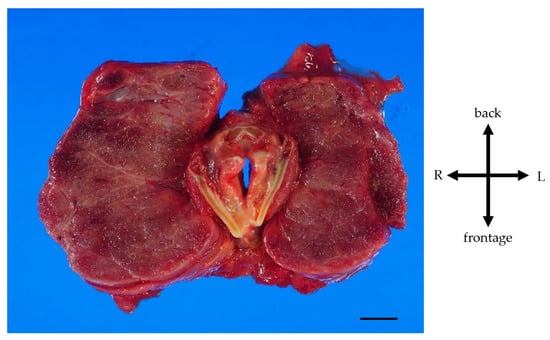

A Case of Giant Goiter Associated with Airway Stenosis Caused by Long-Term Intravenous Epoprostenol Therapy for Idiopathic Pulmonary Arterial Hypertension

Nishiura, K.; Nakazato, K.; Yokokawa, T.; Suzuki, Y.; Kurosawa, Y.; Wada, K.; Shimizu, T.; Oikawa, M.; Kobayashi, A.; Sugimoto, K.; et al. A Case of Giant Goiter Associated with Airway Stenosis Caused by Long-Term Intravenous Epoprostenol Therapy for Idiopathic Pulmonary Arterial Hypertension. J. Clin. Med. 2023, 12, 6359. https://doi.org/10.3390/jcm12196359